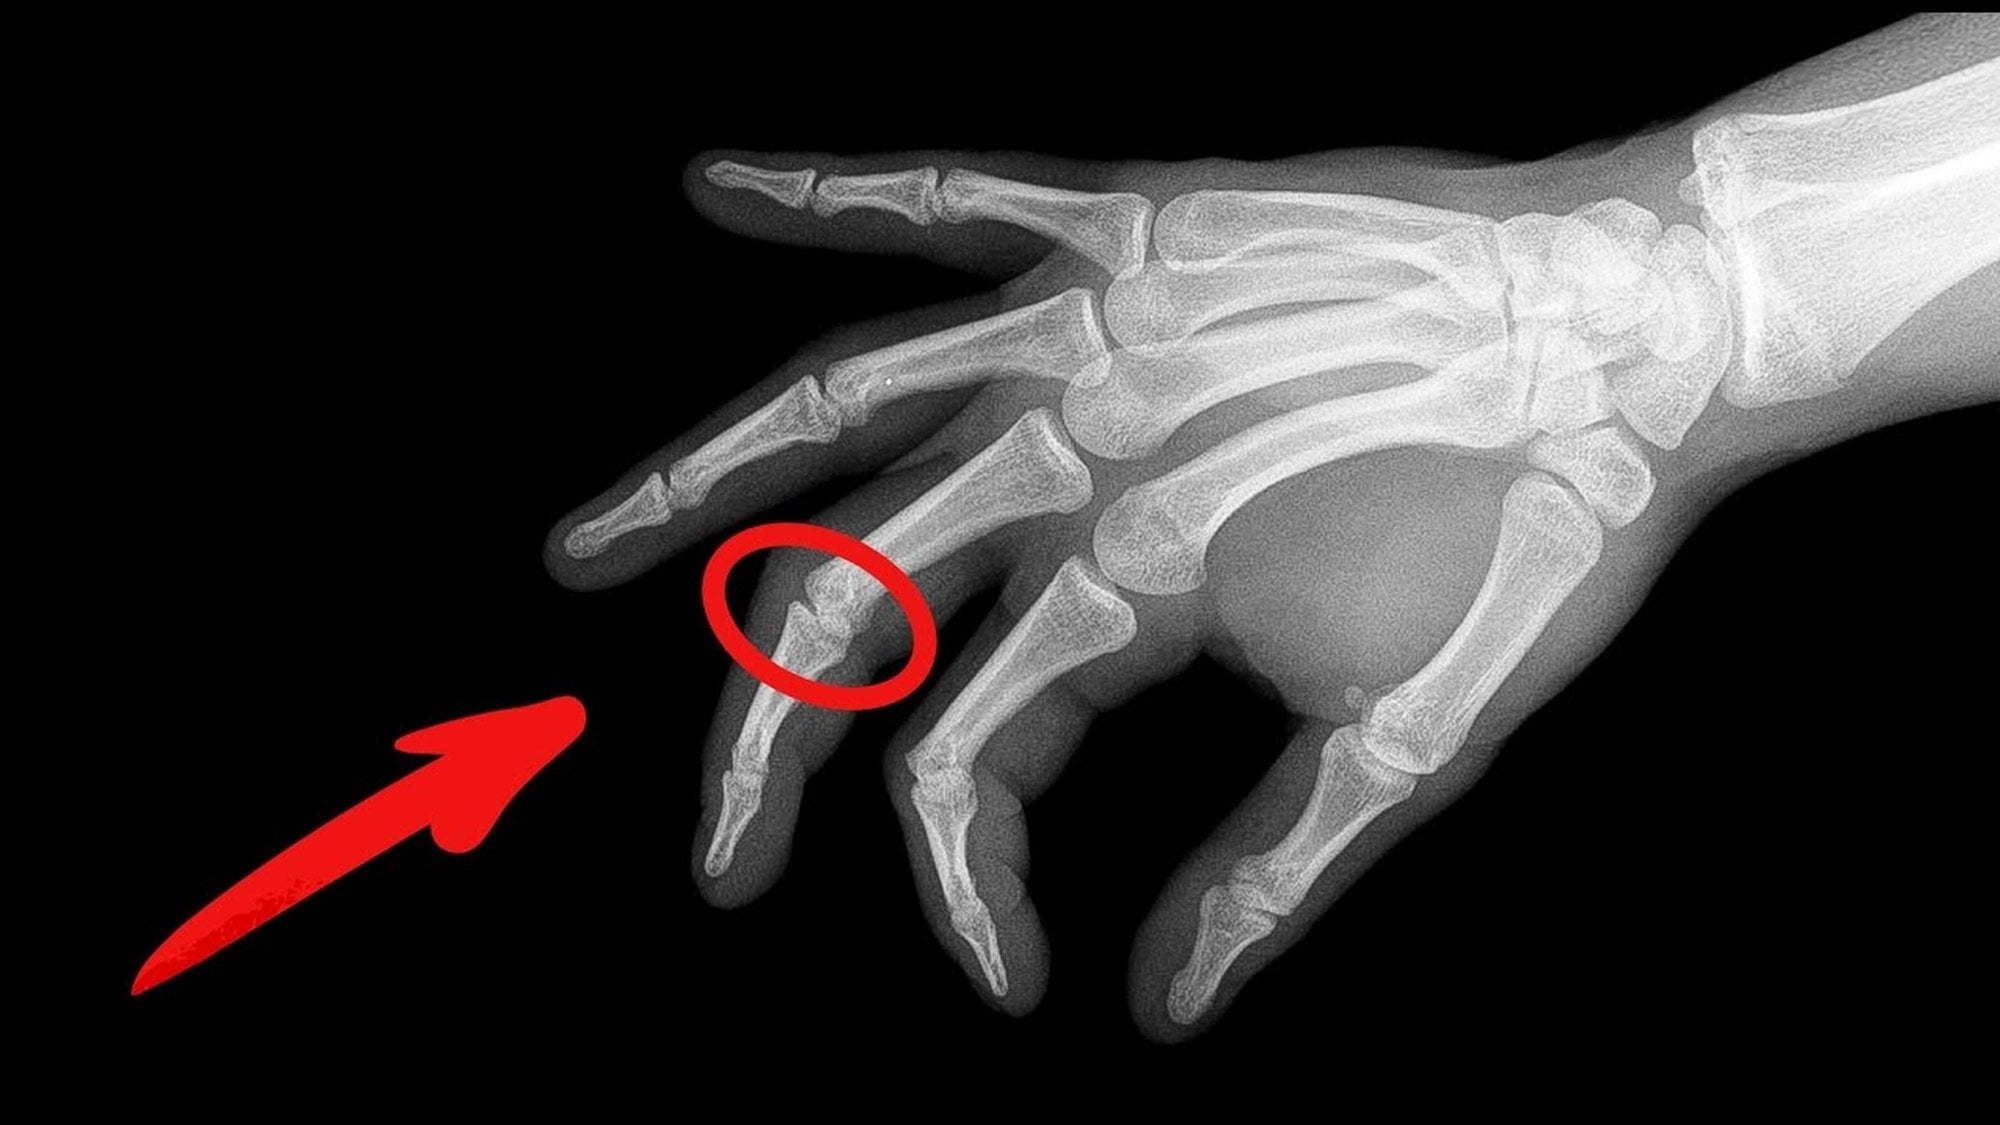

Parmak kütletme ve şıklatma, eklemlerimizde duyulan karakteristik “küt küt” veya “çıt çıt” seslerin kaynağıdır. Bu sesler, parmaklarda baş parmak ile orta veya işaret parmağı arasındaki ani gerilimin serbest bırakılması, boyun ve bel eklemlerinde sinovyal sıvı içindeki gaz kabarcıklarının hızlı patlaması ya da eklem yüzeylerinin hızlı kaymasıyla oluşur. Kulak kütletmeleri ise çoğunlukla çene hareketleri ve orta kulaktaki basınç değişiklikleriyle ilişkilidir. Ayrıca parmak şıklatma, kütletmeye göre daha hafif bir hareket olarak ritim tutmak veya dikkat çekmek amacıyla yapılır ve mekanizması da benzer şekilde kinetik enerji ve hızlı hareketle ses üretimine dayanır.

Parmak kütletme ve şıklatma, hem günlük alışkanlık hem de bilim insanlarının uzun yıllardır merak ettiği bir konudur. İlk bilimsel incelemeler 1940’lı yıllarda Roston ve Wheeler Haines tarafından yapılmış, eklem kapsüllerinde oluşan gaz kabarcıklarının çıtlamanın kaynağı olduğunu göstermiştir. 1970’lerde Unsworth ve meslektaşları, kavitasyon kabarcıklarının çökmesinin sesin oluşumunda etkili olduğunu öne sürmüş, daha yakın zamanlarda Gregory Kawchuk ve ekibi MRI ile gerçek zamanlı görüntüleme yaparak tribonükleasyon mekanizmasını doğrulamıştır. 2018’de Chandran Suja & Barakat, parmak kütletme ve şıklatma seslerini matematiksel olarak modelleyerek mekanizmanın niceliksel bir açıklamasını ortaya koymuştur.